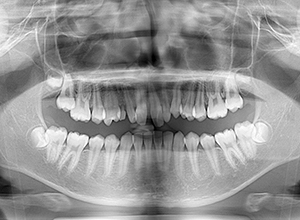

X-Ray

X-Ray所見

パノラマ所見 上下顎第三大臼歯は埋伏歯しており、上顎右側犬歯は先天欠如をしていた。